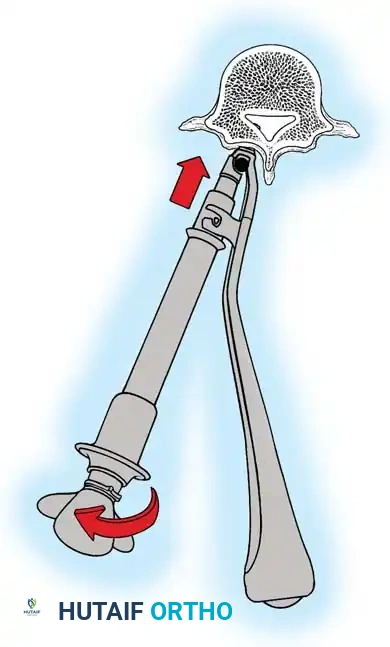

- Cobb Elevation: Utilizing a Cobb elevator combined with electrocautery, expose the spinous processes subperiosteally. Move the cartilaginous caps and attached paraspinal muscles laterally.

- Direction of Dissection: It is anatomically advantageous to dissect from caudad to cephalad. The short rotator muscles (multifidus and rotatores) and ligaments of the spine attach obliquely, pointing superomedially. Sweeping upward works with the grain of these fibers, allowing for a cleaner, faster subperiosteal release.

- Maintaining Tension: As the exposure deepens, sequentially advance the Weitlaner or Cerebellar retractors. Constant, firm retraction is the surgeon's best tool for passive hemostasis.